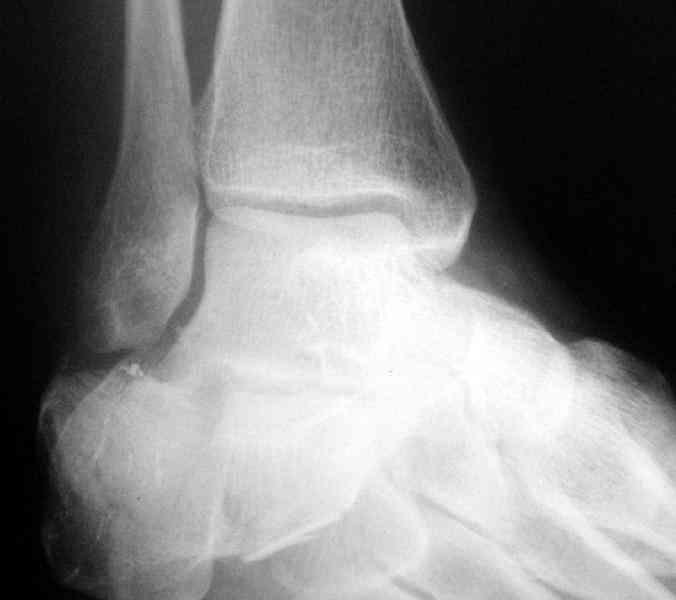

Its a comminuted one.

I would have a CT prior 2 surgery(If u have to postpone a surgery for it - I would operate without one)

I myself would reduce it with EX-FIX and depending on the result would consider a plate on the table.

MOST OF MY COLLEGUES WOULD OPEN IT LATERALLY( a flap) and having a proper reduction would put a plate.

Перелом безусловно внутрисуставной. Киста-не киста принципиального значения не имеет.